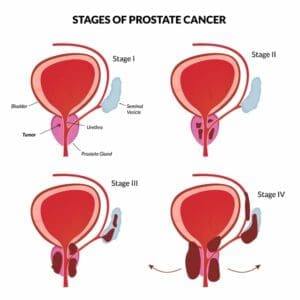

Cancer Staging

There are actually two types of staging for prostate cancer—the clinical and pathologic staging. Clinical staging is the doctor’s best estimate regarding the extent of the prostate cancer based on the results of a physical exam, digital rectal exam (DRE), lab tests, prostate biopsy and imaging tests. Pathologic staging is based on the examination of tissue removed during surgery. Pathologic staging is likely to be more accurate than clinical staging because it enables physicians to get firsthand knowledge about the extent of the cancer.

Pathological Staging

Staging refers to how much the cancer has grown and spread. Is it confined locally within the prostate? Has it spread beyond the prostate and into the lymph nodes, or metastasized to the bones? In cases where the Gleason score is on the high side, additional tests such as an MRI, CT scan or bone scan will be conducted to help stage the prostate cancer more precisely. Based on these reports, the American Joint Committee on Cancer TNM (Tumor, Node, Metastasis) Staging System is used to describe how far the cancer has spread. The TNM system is based on three important pieces of information:T1a – cancer found in 5% of TURP specimens

T1b – cancer found in more than 5% of TURP specimens

T1c – cancer found on prostate needle biopsy only because of elevated PSA

T2a – cancer found in less than 50% of one side of the prostate

T2b – cancer found in more than 50% of one side of the prostate

T2c – cancer found in both sides of the prostate

T3a – cancer has spread outside the prostate, but not to seminal vesicles

T3b – cancer has spread to the seminal vesicles

T4 – cancer has grown into the nearby tissues such as bladder or pelvic sidewall

Nx – lymph nodes have not been assessed for cancer

N0 – no cancer in nearby lymph nodes

N1 – cancer has spread to nearby lymph nodes

Mx – it is unknown if cancer has spread to distant sites

M0 – cancer has not spread to distant sites

M1 – cancer has spread to distant sites

M1a – cancer has spread to distant lymph nodes

M1b- cancer has spread to bones

M1c – cancer has spread to distant organs